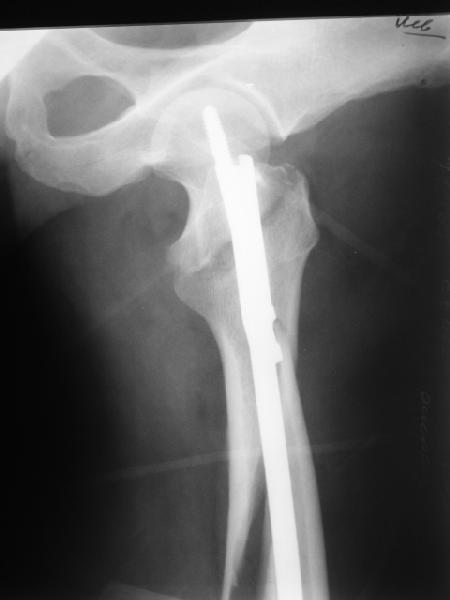

Реконструкционный гвоздь.

Да, сейчас это и у нас самый напрашивающийся выбор. Сделали гвоздем ChM, картинки в приложении.

У молодых реконструкционный гвоздь самое то. При остеопорозе надо что-то помассивнее.